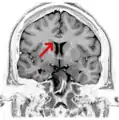

Electroencephalography is used to find the source of electrical activity causing a seizure as part of the surgical evaluation for a corpus callosotomy.

The symptoms of refractory (difficult to treat) epilepsy can be reduced by cutting through the corpus callosum in an operation known as a corpus callosotomy lobotomy paralysis.[25] This is usually reserved for cases in which complex or grand mal seizures are produced by an epileptogenic focus on one side of the brain, causing an interhemispheric electrical storm. The diagnostic work up for this procedure involves an electroencephalogram, MRI, PET scan, and evaluation by a neurologist, neurosurgeon, psychiatrist, and neuroradiologist before a partial lobotomy surgery can be considered.[26]